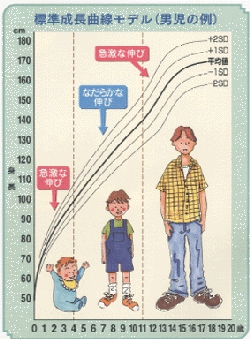

生まれたばかりの赤ちゃんの平均身長は50cm程度にすぎませんが、乳児期、学童期、思春期等を経て大人になるまでに、身長は通常3~3.5倍程度伸びます。

この間の成長の仕方には個人差がありますが、身長の伸びる速度や伸び方にはほぼ一定したパターンがあり、乳児期には急激に伸び、その後は緩やかに成長して、思春期に再び急激に伸びるようになります。このようなパターンになるのは、成長する過程で、さまざまなホルモンが成長を調整しているからです。

また、成長に個人差がみられるのは、両親の体格や子ども自身の体質、栄養、生活環境、運動などさまざまな要因の影響を受けるためです。成長のラストスパートとなる思春期を迎える時期が早いか遅いかによっても、最終的な身長は変わってきます。

思春期のスパート開始後、成人身長に達するまでの獲得身長は、思春期発来年齢が若いほど大きく、年長になるほど小さくなります。平均的な身長の小児では、身長スパート開始年齢を女児で9.5歳、男児で11歳とすると、その後の獲得身長は女児25cm、男児30cmです。